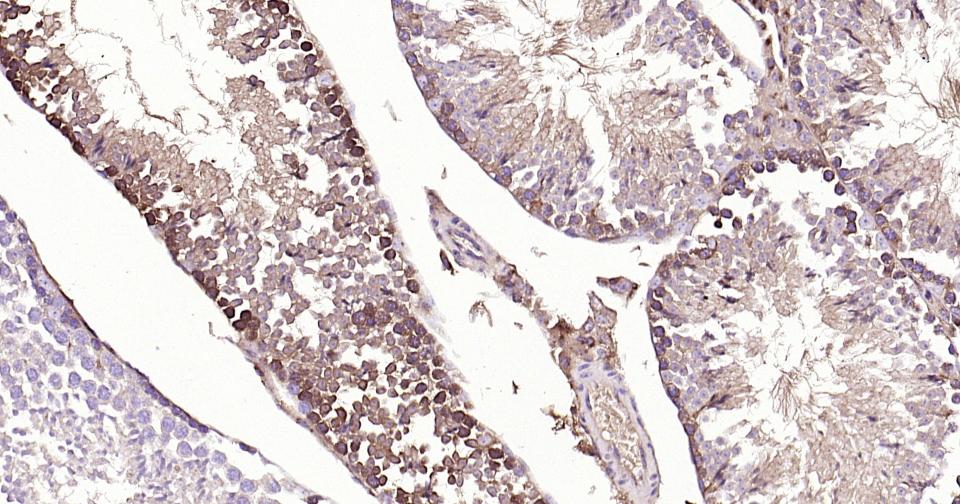

Paraformaldehyde-fixed, paraffin embedded Human Testicles; Antigen retrieval by boiling in sodium citrate buffer (pH6.0) for 15 min; Antibody incubation with Cystatin-C Monoclonal Antibody, Unconjugated(bsm-61363R) at 1:200 overnight at 4°C, followed by conjugation to the SP Kit (Rabbit, SP-0023)and DAB (C-0010) staining.

Paraformaldehyde-fixed, paraffin embedded Mouse Testicles; Antigen retrieval by boiling in sodium citrate buffer (pH6.0) for 15 min; Antibody incubation with Cystatin-C Monoclonal Antibody, Unconjugated(bsm-61363R) at 1:200 overnight at 4°C, followed by conjugation to the SP Kit (Rabbit, SP-0023)and DAB (C-0010) staining.